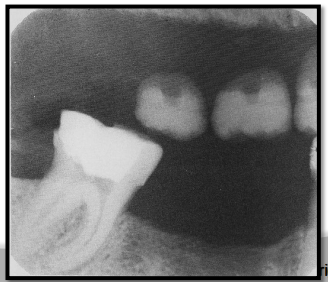

How are stainless steel and chrome crowns differentiated on a radiograph from amalgam or gold restorations?

SS crowns and chrome crowns have smooth and regular margins

usually used as a temporary restoration

Thin and do not absorb as much xrays → appear radiopaque but not as densely as amalgam or gold

may have some “see-through”ish areas on radiograph.